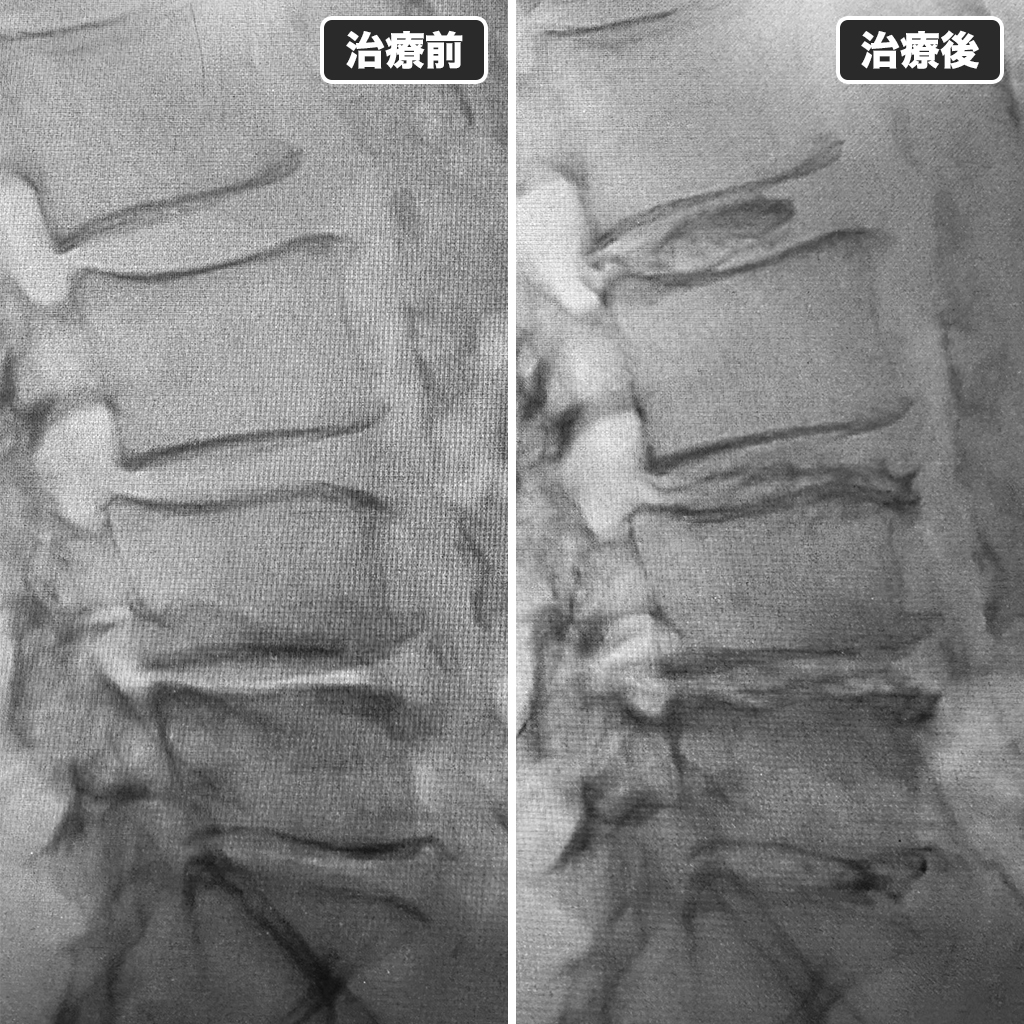

治療前後のレントゲン写真

治療前後のレントゲン比較です。左側が治療前、右側が治療後になります。

治療時間は14分ほどでした。ゴルフの再開は3月頃に予定していただくようにお願いしました。